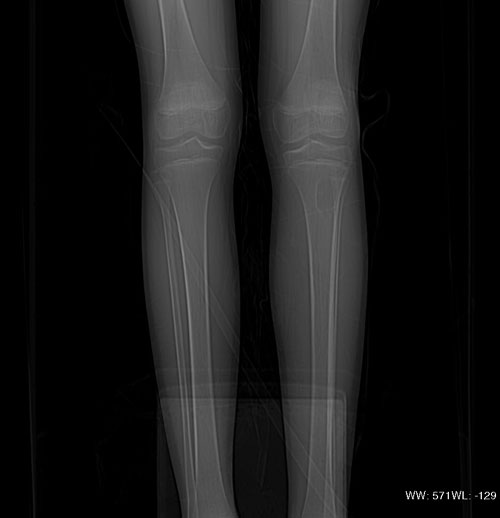

以下是引用37度在2010-1-7 12:22:00的发言:[br]左胫骨上段纤维性骨皮质缺损(非骨化性纤维瘤).

以下是引用dyqct在2010-1-7 14:54:00的发言:[br]考虑为左胫骨上段纤维性骨皮质缺损 ,可自愈.

以下是引用xkncyyhyq在2010-1-7 9:54:00的发言:[br]考虑为纤维性骨皮质缺损